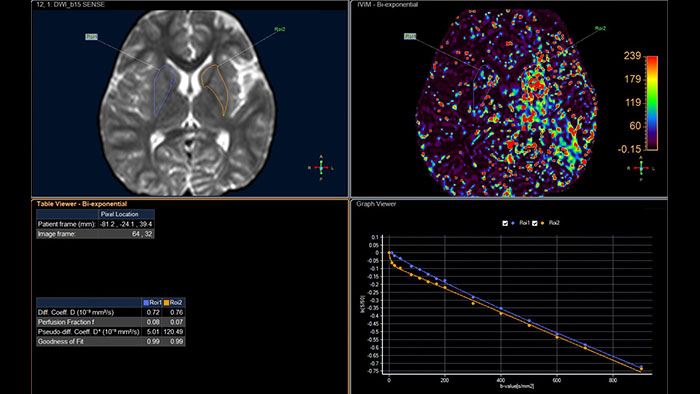

Advanced Diffusion Analysis (ADA)

MR Advanced Diffusion Analysis

Computed diffusion weighted images at a b-value of choice

The application is intended to view, process and analyze MRI Diffusion Weighted Images. It calculates and displays cDWI at a

b-value of choice (from 0 to 5,000 s/mm2) and provides advanced supportive analysis and visualization tools of diffusion MRI images and parametric maps.

• Presents a default diffusion analysis model based on the available original DWI images as well as a selection of alternative models including monoexponential, biexponential, simplified IVIM, and kurtosis.

• A ‘goodness of fit’ value and fitted curve show the fitting quality of the selected model.

• Provides parametric maps of perfusion fraction (f), pseudo diffusivity (D*), Diffusivity (D) and Kurtosis (K).